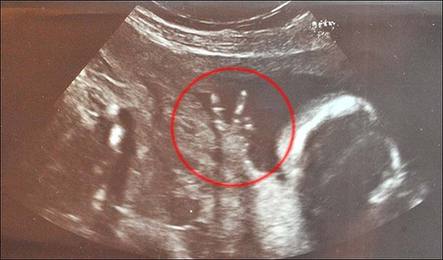

中國日報網環球在線消息: 這恐怕是世界上最自信狂野的寶寶——他(她)還在媽媽肚子里時就比出了完美的V字型手勢,仿佛在向世人宣稱:“嘿,我可就要來到世上了哦,準備接招吧各位!”

據英國《太陽報》7月9日報道,懷孕已經23周的英國女子卡洛琳?巴恩斯近日來到醫院做定期的超聲波檢查,結果發現肚子里的寶寶居然從始至終都豎著兩根小手指頭,擺出了絕對到位的V字型手勢。

今年35歲的卡洛琳為倫敦當地的一家電視臺工作,她告訴記者:“在場的護士都笑個不停。做檢查的整個過程中,寶寶的手勢一直都是那樣。”